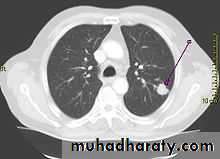

• A-Asymptomatic• Any smooth homogenous opacity of uniform density with clear cut border and little or no reaction around it on a chest X-Ray is a hydatid cyst unless proved the other wise .

• Radiological Findings

• 1-Smooth homogenous opacity (Intact H.C).• 2-Partial rupture (peri-vesicular pneumocyst).